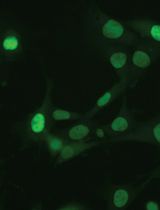

TRIPLE (Insulin, Glucagon and EGFP) Immunofluorescence Staining Protocol in Pancreas

胰腺的三重(胰岛素、胰高血糖素和增强型绿色荧光蛋白(EGFP))免疫荧光染色法